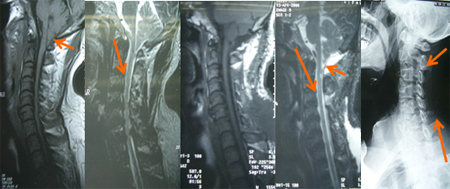

男性,43岁,双上肢麻木、无力5年,渐延至下肢1年,走路不稳3月。入院查体:Romberg征(+),双上肢片状针刺痛觉减退,双上肢近端肌力4级、远端3+级,双下肢近端5级、远端4-,双侧Hoffman征(+)、Babinskii征(+)。术前图片:小脑扁桃体疝入椎管内,枕大孔平面下5mm多、颈椎管广泛狭窄;行颈后路枕颈减压、枕大池成型、单开门椎管扩大成型术;术后图片示:颅颈交界骨性、软性空间都获扩大,椎管空间扩大。